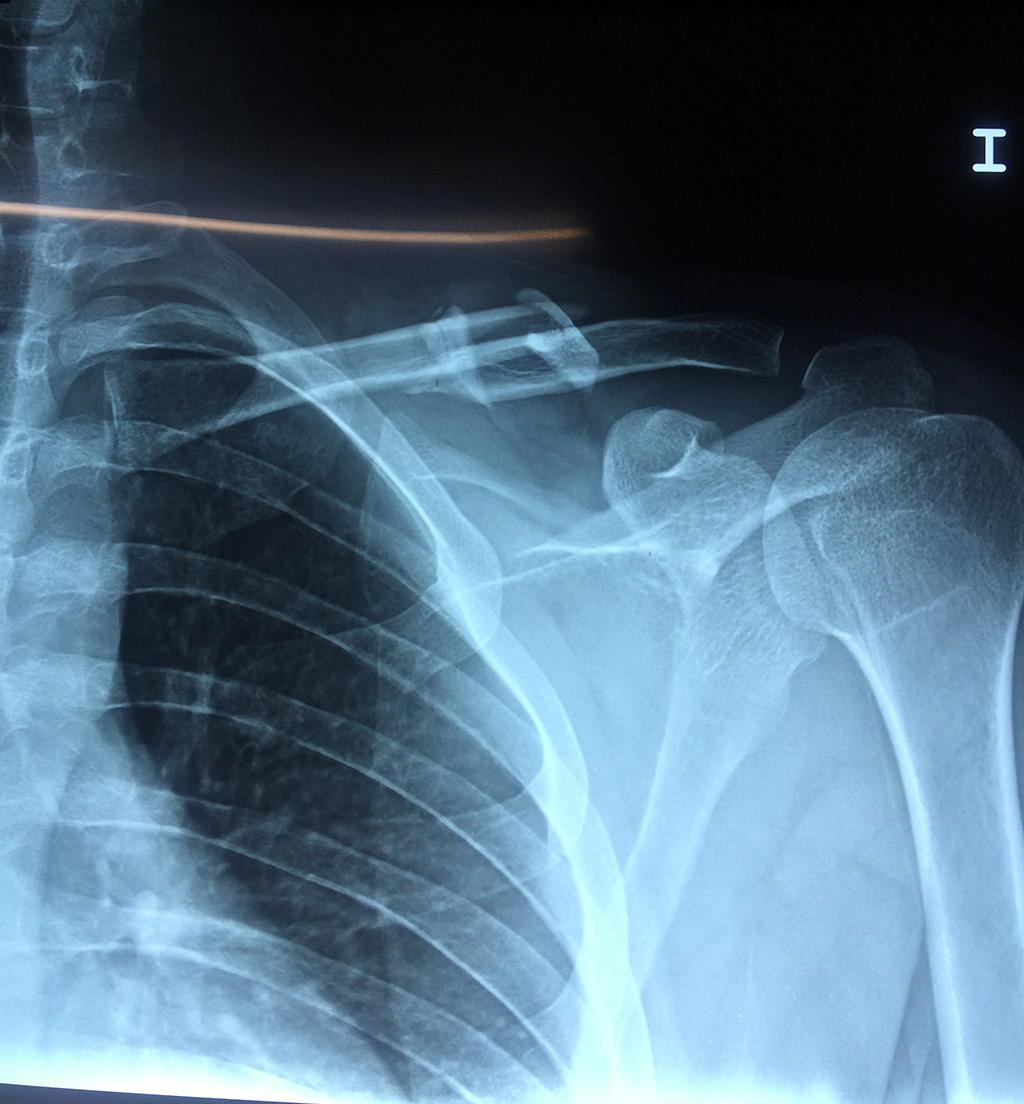

Clavícula

La clavícula es un hueso largo, con forma de "S" itálica, situado en la parte anterosuperior del tórax. Junto con la escápula forman la cintura escapular. Se puede palpar por toda su longitud y se extiende del esternón al acromion de la escápula, siguiendo una dirección oblicua lateral y posterior.

Se considera el único medio de unión entre el miembro superior y el tórax. A pesar de su aspecto, similar al de un hueso largo, posee una estructura semejante a la de un hueso plano, ya que carece de epífisis y de diáfisis, lo que la harían entrar dentro de la clasificación de hueso largo. Carece de un canal medular propiamente dicho.